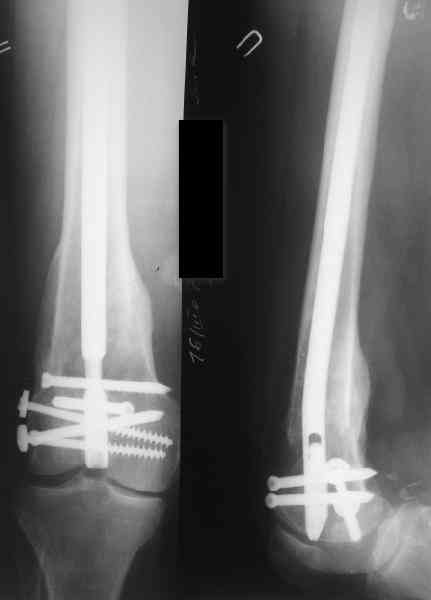

27 марта выполнено удаление блокирующих винтов (сломанный винт пришлось высверливать цапфен-бором), сломанного штифта (дистальный фрагмент удален через канал, образованный разверткой из коленного сустава - image 4),

рассверливание костно-мозгового канала, реостеосинтез штифтом UFN (при проведении штифта в дистальном отломке мы использовали поляризующий винт, диаметр штифта 10 мм). После операции в связи гемартрозом дважды (на 1 и 3 сутки) выполняли пункцию коленного сустава. Сейчас признаков скопления жидкости в полости сустава нет. Послеоперационные рентгенограммы - images 5, 6, 7.

Все здорово! Но, 1)- почему штифт 10мм, а не больше?, 2) - проксимальное блокирование одним вмнтом в статическом положении?

1) Мы располагали штифтом только данного диаметра.

2) По-поводу проксимлаьного блокирующего винта. Винт стоит на 3-5 мм выше нижнего

края динамического отверстия. Препятствий для компрессии отломков пока нет.